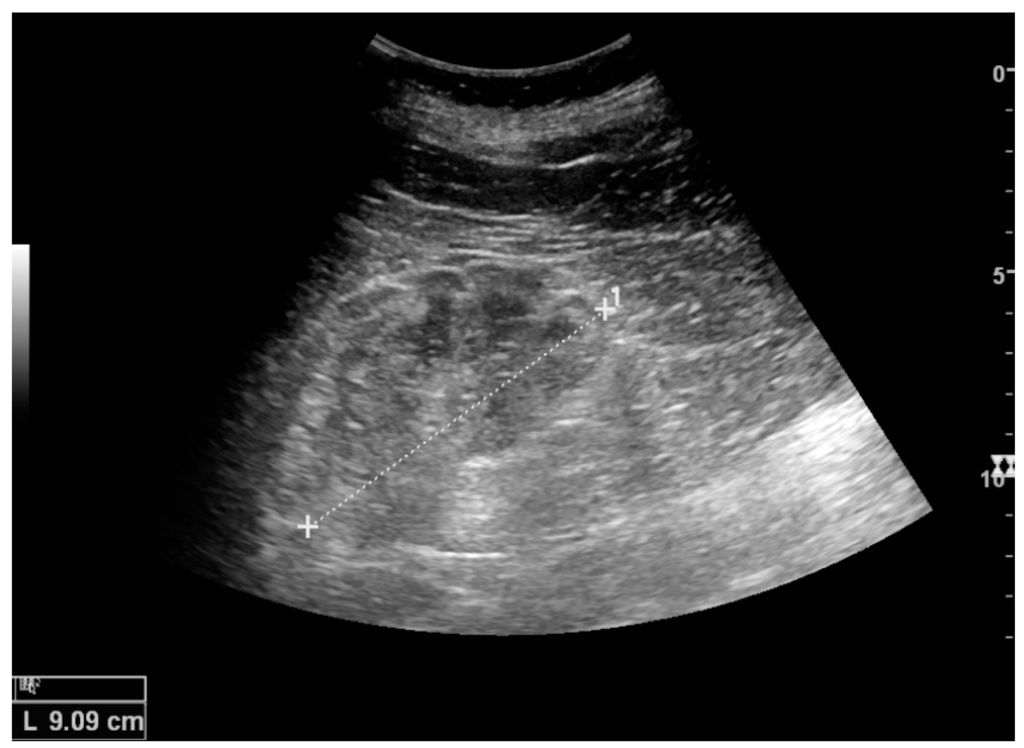

The hydronephrosis is typically graded visually and can be divided into five categories going from a slight expansion of the renal pelvis to end-stage hydronephrosis with cortical thinning (Figure 15) [16]. The evaluation of hydronephrosis can also include measures of calyces at the level of the neck in the longitudinal scan plane, of the dilated renal pelvis in the transverse scan plane and the cortical thickness, as explained previously (Figure 16 and Figure 17) [4].

Figure 15. End-stage hydronephrosis with cortical thinning. Measurement of pelvic dilatation on the US image is illustrated by ‘+’ and a dashed line.